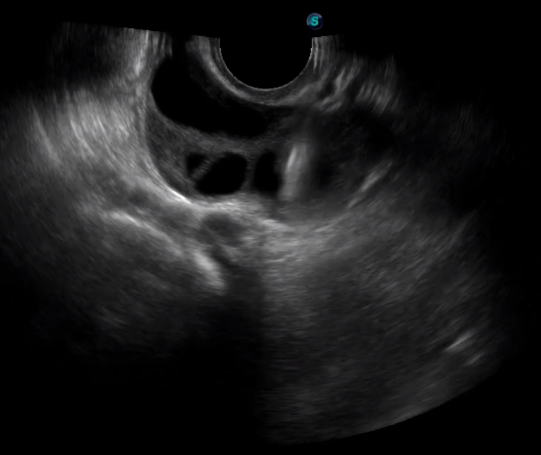

5   TEE

TEE(經(jīng)食道超聲心動圖)將超聲探頭置入食道內(nèi),從心臟的后方向前近距離探查其結(jié)構(gòu) ,克服了經(jīng)胸超聲檢查的局限性,避免肺內(nèi)氣體、胸壁脂肪、胸廓畸形等因素影響,觀察角度更多,圖像更加清晰,測量數(shù)據(jù)更準確。

經(jīng)食道超聲 大動脈短軸